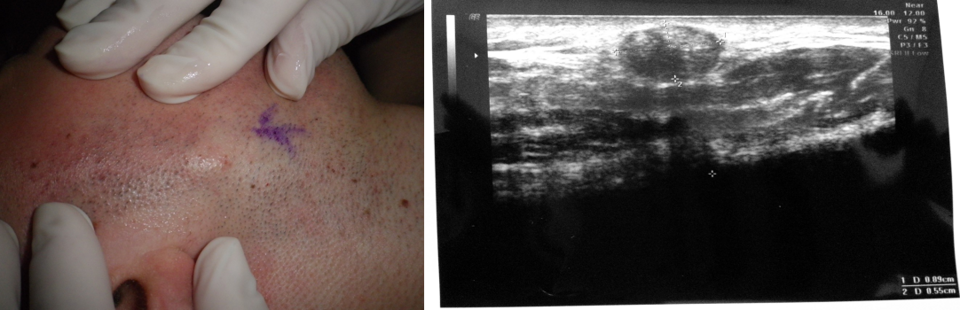

Metastasi da melanoma: metastasi in transit a 1 cm dalla cicatrice chirurgica con aspetto nodulare solida e con eco struttura omogenea e ipoecogena.

Corpi estranei (es. pallino da caccia): i corpi metallici riflettono completamente gli echi e generano fenomeni di "scattering".